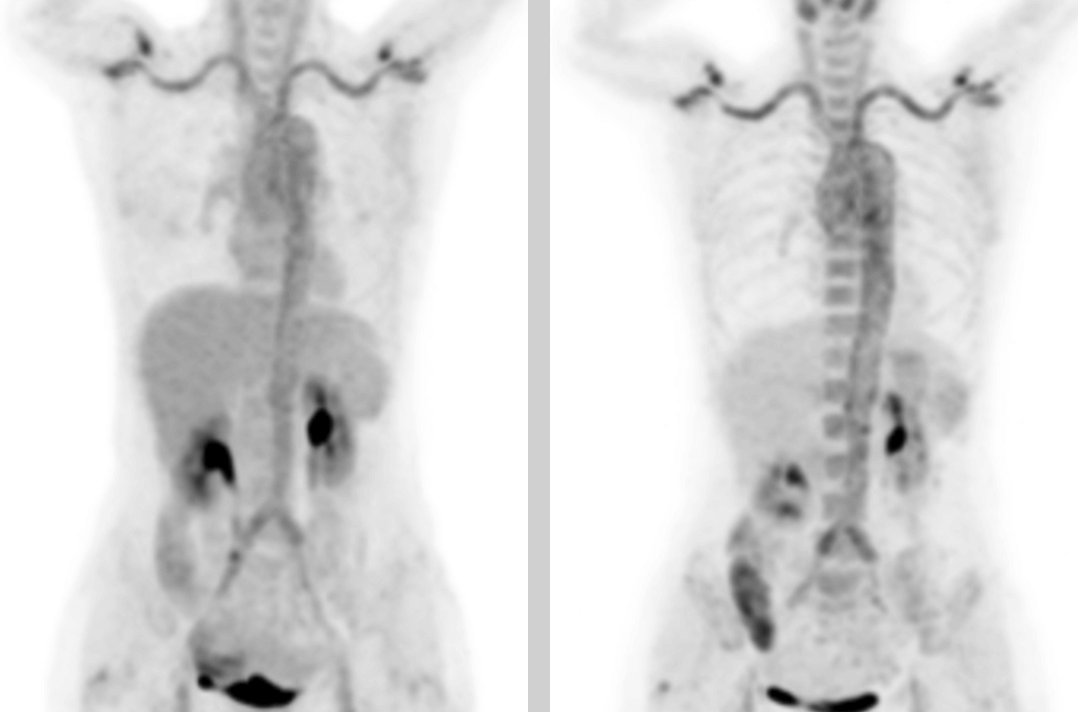

Gdy we wczesnym stadium nie występują zmiany morfologiczne w naczyniach, zwykłe badania obrazowe nie są wystarczająco czułe na ich zapalenie, co nie sprzyja wczesnemu rozpoznaniu tego zespołu. Wykorzystanie multimodalnego badania PET/TK oraz połączenie informacji anatomicznych i funkcjonalnych (dotyczących metabolizmu) może skutecznie uwidocznić przejawy hipermetabolizmu ścian naczyń w ich zapaleniu oraz ocenić cechy morfologiczne naczyń krwionośnych. Dysponując długim osiowym polem widzenia oraz wysoką czułością i rozdzielczością, cyfrowy system PET/TK firmy United Imaging może dodatkowo ułatwiać obrazowanie nieprawidłowego metabolizmu makronaczyniowego podczas opóźnionego skanowania, dostarczyć półilościowe wskaźniki do diagnozy zespołu Takayasu i skutecznie poprawić dokładność diagnostyczną.

W obrazach PET/TK w kilku lokalizacjach (obustronna tętnica szyjna wewnętrzna, tętnica szyjna wspólna, pień ramienno-głowowy, obustronne tętnice podobojczykowe i pachowe, aorta piersiowa, aorta brzuszna, obustronna tętnica biodrowa wspólna, tętnica biodrowa wewnętrzna, tętnica biodrowa zewnętrzna i tętnica udowa) wystąpiło pogrubienie ściany ze zwiększonym metabolizmem glukozy, co uznano za spowodowane zmianami zapalnymi. Na podstawie wywiadu lekarskiego, objawów klinicznych, badania i wyników badań obrazowych u pacjentki rozpoznano zespół Takayasu. Po zastosowaniu standardowego leczenia przeciwzapalnego temperatura ciała spadła, a stan pacjentki uległ poprawie.

Przedstawiony przypadek jest typowym przykładem zastosowania PET/TK ze znacznikiem F-FDG w diagnostyce zespołu Takayasu.

Badanie PET/TK z F-FDG może umożliwić zdiagnozowanie zespołu Takayasu i ocenić chorobę w jej fazie aktywnej. Ponadto skanowanie całego ciała może również pozwolić na określenie obszaru zmian chorobowych, stanowić podstawę do ustalenia lokalizacji biopsji tętnicy oraz zapewnić monitorowanie odpowiedzi organizmu pacjentki na leczenie. Może też umożliwić jakościowe rozpoznanie zwiększonego metabolizmu w miejscu dotkniętym chorobą. Półilościowy wskaźnik maksymalnego standardowego wychwytu SUVmax jest przydatniejszy od wskaźników surowicy krwi, takich jak ESR i CRP, w czułym i swoistym wykrywaniu zespołu Takayasu, co może zwiększyć dokładność diagnostyczną.